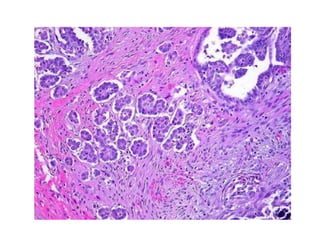

Adenocarcinoma endometrioide

do endométrio

Carcinoma seroso do endométrio